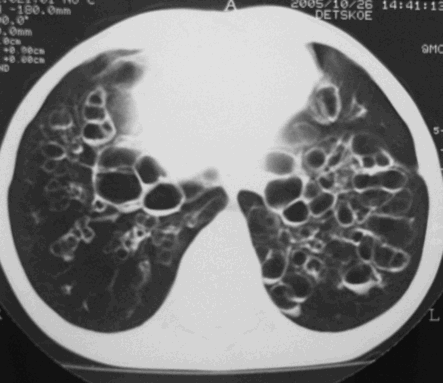

Кистозная гипоплазия легких